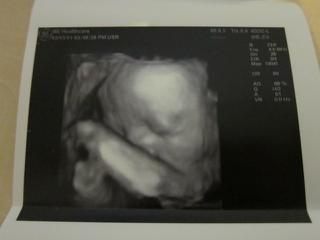

bolo to uzasne, 😵 fakt to stalo za to, sestricka najprv vsetko pomerala, skontrolovala, babo je v poriadku a definitivne sa potvrdilo ze to bude nase vytuzene dievcatko, 😵 podla sestricky je to iste na 1000%. 🙂

Babo sa nenechalo rusit a cele sono prespinkalo, (ani sa necudujem, mali sme rusnu noc, chytila ma choroba tak so mnou ponocovala, 😅 ),

na videu je sice stale kludnucka a len sem tam sa pohmyri ale aspon sa lepsie dalo zachytit foto, aj ked si davala stale rucicku pred tvaricku a niekedy tam ta rucicka zavadzala. 😉

Ale aj tak som maximalne spokojna, stale sa neviem vynadivat na bambulku, 😵 je uzasna, meria 37 cm a vazi 1150 g, zodpoveda 27tt, (dnes zacinam 28 tt tak mi to sedi.)

Kuk na foto a dufam ze pridas aj ty. 🙂

Ta prva foto je trochu rozmazana nozicka a foto pod nou dokaz kavoveho zrnka, 😉 na dvd je to lepsie vidiet, tam je to z roznych uhlov. 😉